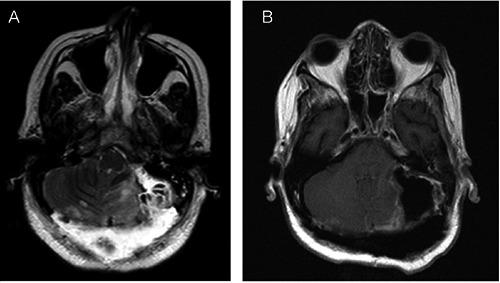

A 56-year-old Afro-Trinidadian woman with a history of a carbidopa-levodopa resistance Parkinsonian-like syndrome for 2 years, presented with acute onset spastic quadriplegia and decreased responsiveness. Diagnosis involved clinical and MR-imaging correlation consistent with a large left posterior fossa meningioma. Surgical removal of the tumor led to complete reversibility of the neurological manifestations associated with cerebellar tonsillar herniation beyond the foramen magnum and mass effect on the brainstem, cerebellum and midbrain regions. Pathological findings were typical of a meningioma. This case demonstrates the association of a large left posterior fossa meningioma and carbidopalevodopa resistant parkinsonism in an Afro-Trinidadian woman who presented with acute onset acute quadriplegia and decreased responsiveness. This case reminds clinicians that patients with dopa unresponsiveness and/or acute neurological deficit or deterioration should be worked up for other possible causes and adds to the literature on the association of parkinsonism and intracranial space occupying lesions.

一名56岁的非裔特立尼达妇女,患有对卡比多巴-左旋多巴耐药的帕金森样综合征2年,出现急性起病的痉挛性四肢瘫和反应迟钝。诊断通过临床与磁共振成像相关性得出,符合左侧后颅窝大型脑膜瘤。手术切除肿瘤后,与小脑扁桃体疝出枕大孔及对脑干、小脑和中脑区域的占位效应相关的神经学表现完全可逆。病理结果为典型的脑膜瘤。该病例显示了一名非裔特立尼达妇女左侧后颅窝大型脑膜瘤与卡比多巴-左旋多巴耐药帕金森病的关联,该妇女表现为急性起病的急性四肢瘫和反应迟钝。该病例提醒临床医生,对多巴无反应和/或有急性神经功能缺损或恶化的患者应排查其他可能病因,并为帕金森病与颅内占位性病变的关联文献增添了内容。